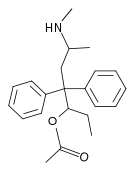

Amidones

Structures

| Amidones | ||||

Methadols

Structures

| Other open chain opioids | ||||

|---|---|---|---|---|

|

|

|

Noracetylmethadol | |